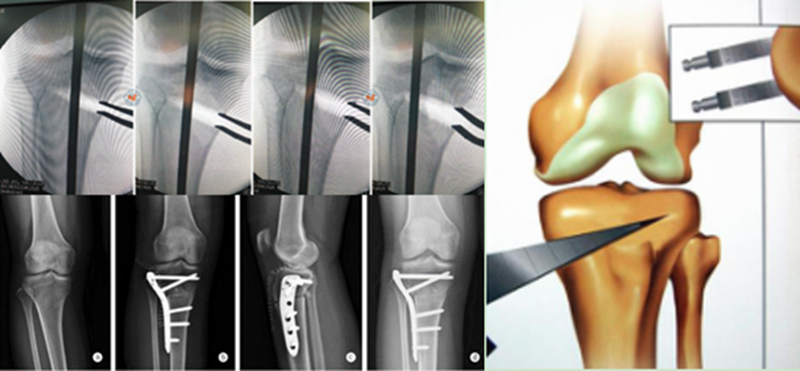

A.双平面截骨,第一刀沿水平面在胫骨后2/3进行截骨,保留外侧合页约10mm,第二刀沿冠状面在胫骨前1/3进行截骨,两刀截骨角度呈110°。B.撑开器逐渐缓慢加大骨缝,注意保留外侧合页。C.力线杆定位,撑开至力线杆经过Fujisawa点。D.进行内固定。

病例1:46岁,滑雪运动员,多发韧带伤,内翻畸形膝关节疼痛,开式截骨后二月全负重行走,膝关节疼痛缓解

病例2:男性,19岁,因发现右膝关节内翻、过伸畸形伴跛行5年(左侧膝关节也有类似畸形,暂时无症状)。于2006年7月就诊,其母亲也有类似病史。查体:右膝关节内翻畸形约15度,应力下过伸约20度,内翻及外翻时膝关节均有松动感,Lanchman试验(+)。无负重下X片示:右膝关节内翻畸形约15度,胫骨平台无后倾,倒呈前倾13º。膝关节MR示:右膝内侧股骨及胫骨软骨面已有缺损并囊性变。诊断:先天性膝关节内翻畸形(Blount病)。

术前X线可见右膝关节内翻畸形约15°,胫骨平台前倾畸形13°

术前膝关节MR示:右膝内侧胫、股骨骨软骨面已有缺损并囊性变

应力位过伸畸形明显

术后6月X片示右膝内翻、前倾畸形已矫正,胫骨截骨处愈合,腓骨未愈合,但无症状。